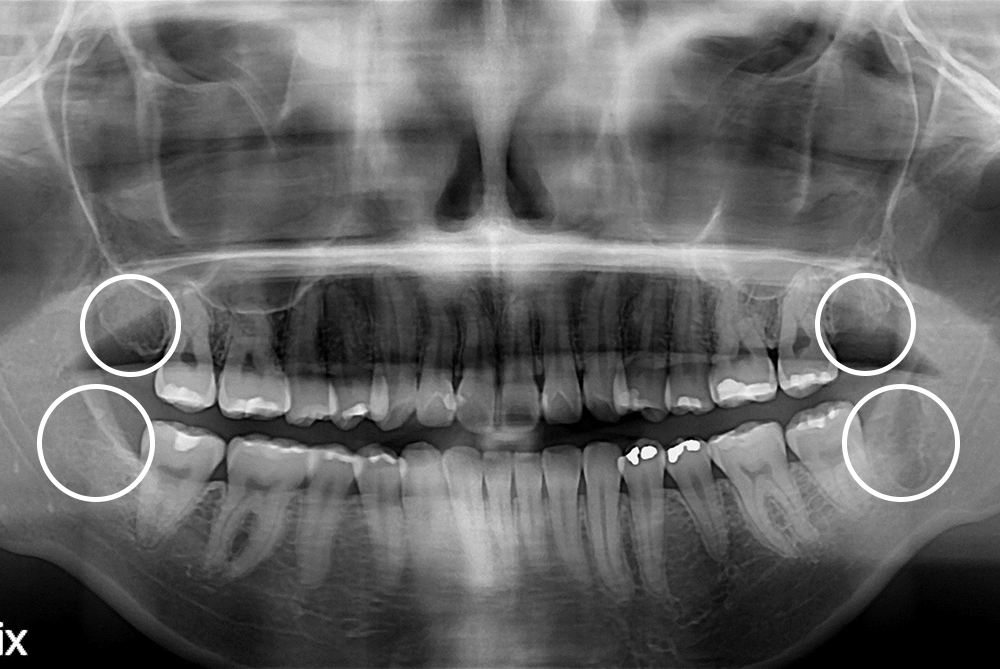

[사랑니] 매복 사랑니 발치

치료전 : 2018-12-20